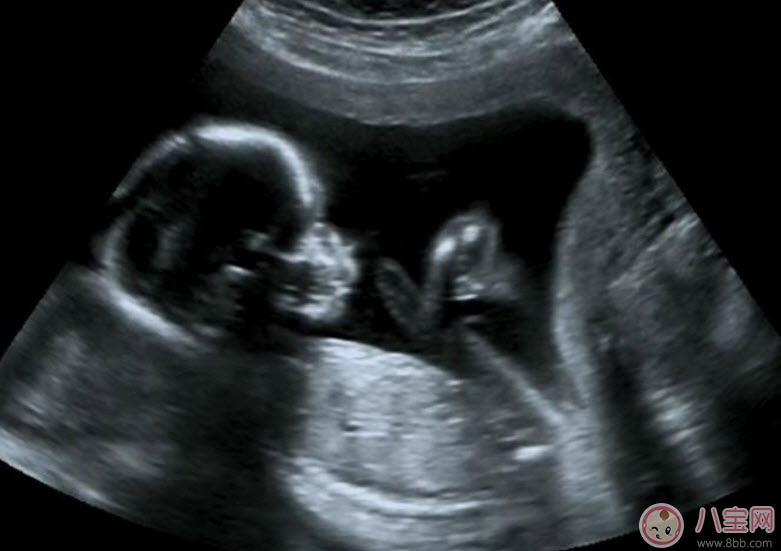

經(jīng)陰道超聲是通過(guò)超聲機(jī)上的特殊探頭而實(shí)現(xiàn)的。在陰道超聲探頭上套上薄膜,將探頭伸入陰道進(jìn)行檢查。由于探頭位置接近子宮和卵巢,圖像清晰分辨率高,檢查結(jié)果較準(zhǔn)確。除此之外,它還有另一個(gè)優(yōu)點(diǎn)是不需要憋尿,相對(duì)節(jié)省時(shí)間,患者感覺(jué)也好。

為監(jiān)測(cè)孕囊的部位、胎兒的生長(zhǎng)發(fā)育情況,降低畸形兒和有缺陷兒的出生率,早孕期陰道B超檢查顯然是很必要的。早孕期做陰道B超檢查有以下幾點(diǎn)好處:

2.核實(shí)孕周、判斷胚胎發(fā)育情況。根據(jù)孕囊的平均直徑、胎芽大小、胎兒的頭臀長(zhǎng)判斷孕齡,有助于中晚孕期間判斷胎兒發(fā)育的狀況。經(jīng)陰道B超胎芽大于5mm時(shí),應(yīng)該見(jiàn)到胎心搏動(dòng)。如果沒(méi)有見(jiàn)到胎心搏動(dòng),提示有胚胎停止發(fā)育 的可能,應(yīng)定期復(fù)查。